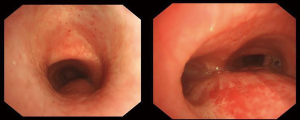

After the informed consent was obtained from the patient and her family, an individualized therapeutic strategy was designed. Total laryngopharyngoesophagectomy combined with low AMT was performed under general anesthesia. The esophagus was mobilized under a thoracoscope, and the tubular stomach was created laparoscopically. After a Y-shaped incision was made in the cervical thorax, the anterior cervical muscles were dissected, and the thyroid gland was preserved. Afterward, the cervical systemic lymph node dissection was done. After total laryngectomy, the trachea was resected about 3 cm above the carina, and the trachea was intubated intraoperatively for ventilation. The sternoclavicular joint, the sternal stalk and the medial portions of rib cartilage were all removed, but the clavicle was preserved. Then, the tubular stomach was uplifted to the neck via the posterior mediastinal route for manual anastomosis. Double S-shaped pectoralis major musculocutaneous flap were harvested at the upper edge of the sternal stump for repairing the tracheal stump (Figure 4). A low AMT was performed on the chest. During this process, the trachea traveled inferior to the left innominate vein and right to the brachiocephalic trunk. The greater omentum was preserved for filling the anterior mediastinal area during the tubular stomach uplifting, while the bilateral sternocleidomastoid muscles were also used to fill the anterior mediastinal area. Thus, the tubular stomach was isolated from the trachea (Figure 5). Negative pressure drainage was placed on both sides of the anastomosis, above and below the tracheostomy and under the skin for good drainage (Figure 6). A second chest CT was performed on the tenth postoperative day, showing that the tracheostomy was well healed, and the mediastinal area was well filled with no cavity (Figure 7).